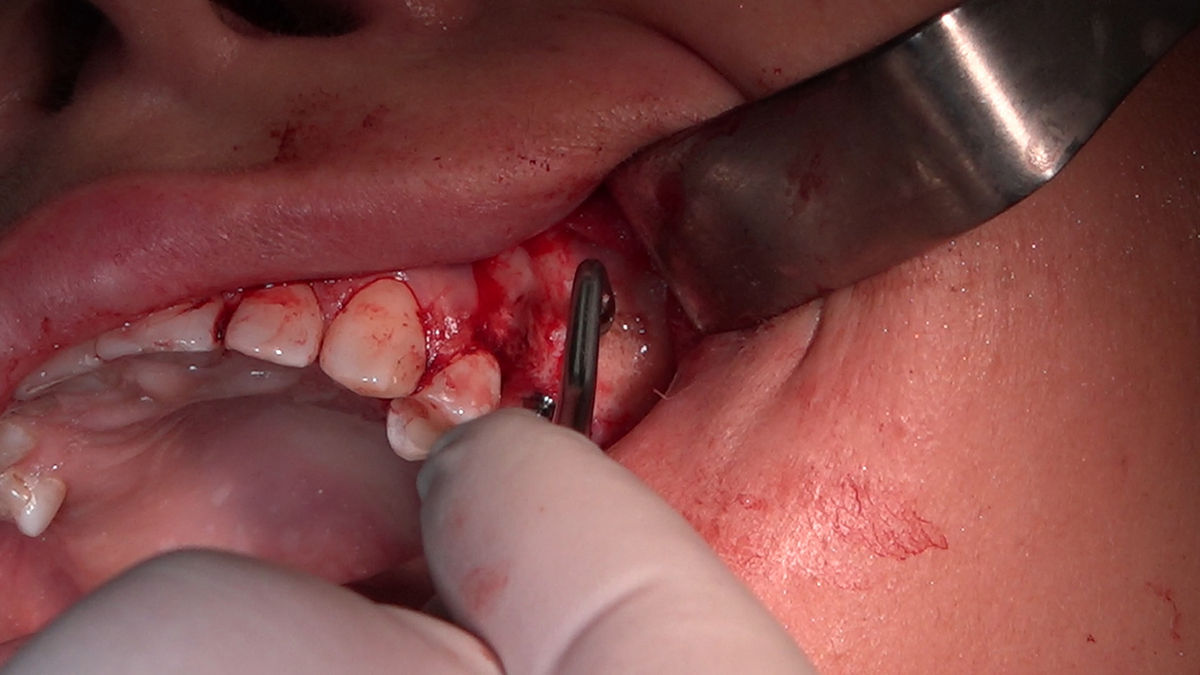

Chirurgia implantologiczna to temat wiodący 5 Sesji X Sezonu Practiculum Implantologii, która się odbyła 23-24 października 2020 roku. Bierze w nim udział 16 adeptów implantologii stomatologicznej. Zabiegi z udziałem Pacjentów jak zwykle poprzedziło omówienie i planowanie, tym bardziej, że zgodnie z planem wykonana została implantacja z wykorzystaniem szablonu chirurgicznego, który przygotowało laboratorium dentystyczne Wiligała Lab. Kursanci wykonywali szereg zabiegów implantologicznych i chirurgicznych oraz regeneracyjnych z zastosowaniem PRF, w tym sinus lift. Przeprowadzali je pod kierunkiem Lidera Umiejętności Implantologicznych dr n.med. Violetty Szycik, która wysoko oceniła wykonanie zabiegów.